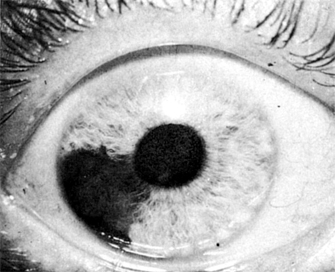

Figure 7-4

Figure 7-4: Posterior synechiae (anterior view). The iris is adherent to the lens in several places as a result of previous inflammation, causing an irregular, fixed pupil. Appropriate treatment with corticosteroids and cycloplegic agents can often prevent such synechiae.

Anterior uveitis is most common and is usually unilateral and acute in onset. Typical symptoms include pain, photophobia, and blurred vision. Examination usually reveals circumcorneal redness with minimal palpebral conjunctival injection or discharge. The pupil may be small (miosis) or irregular due to the formation of posterior synechiae. Inflammation limited to the anterior chamber is called "iritis"; inflammation involving both the anterior chamber and the anterior vitreous is called "iridocyclitis." Corneal sensation and intraocular pressure should be checked in every patient with uveitis. Decreased sensation can suggest herpes simplex or herpes zoster infection, whereas increased intraocular pressure can occur with herpes simplex, herpes zoster, or toxoplasmosis, with sarcoidosis, or with an uncommon form of iridocyclitis called glaucomatocyclitic crisis, or Posner-Schlossman syndrome. Clumps of white cells and inflammatory debris-keratic precipitates-are usually evident on the corneal endothelium. Keratic precipitates may be large ("mutton fat," or granulomatous), small (nongranulomatous), or stellate. Granulomatous or nongranulomatous keratic precipitates are usually located inferiorly, particularly in a wedge-shaped region known as Arlt's triangle. Stellate keratic precipitates are usually distributed evenly over the entire corneal endothelium. They are seen in uveitis due to herpes simplex virus, herpes zoster virus, toxoplasmosis, Fuchs' heterochromic iridocyclitis, and sarcoidosis. Iris nodules may be present at the iris margin (Koeppe nodules), within the iris stroma (Busacca nodules), or in the anterior chamber angle (Berlin's nodules). Evidence for granulomatous disease, such as mutton fat keratic precipitates or iris nodules, may indicate sarcoidosis or an infectious cause of uveitis. Particularly severe anterior chamber inflammation may result in layering of inflammatory cells in the inferior angle (hypopyon). The iris should be examined carefully for evidence of atrophy or transillumination, which can occur in the setting of herpes simplex or herpes zoster virus infection, or with Fuchs' heterochromic iridocyclitis. The presence of anterior or posterior synechiae (Figures 7-2,7-3 to 7-4) should also be noted, as this can predispose the patient to glaucoma.

Anterior uveitis can produce both anterior and posterior synechiae (Figures 7-2,7-3 to 7-4). Anterior synechiae can impede aqueous outflow at the chamber angle and cause glaucoma. Posterior synechiae, when extensive, can also cause secondary angle closure glaucoma, usually by producing pupillary seclusion and forward bulging of the iris (iris bombé). Early and aggressive use of corticosteroids and cycloplegics lessens the likelihood of these complications.